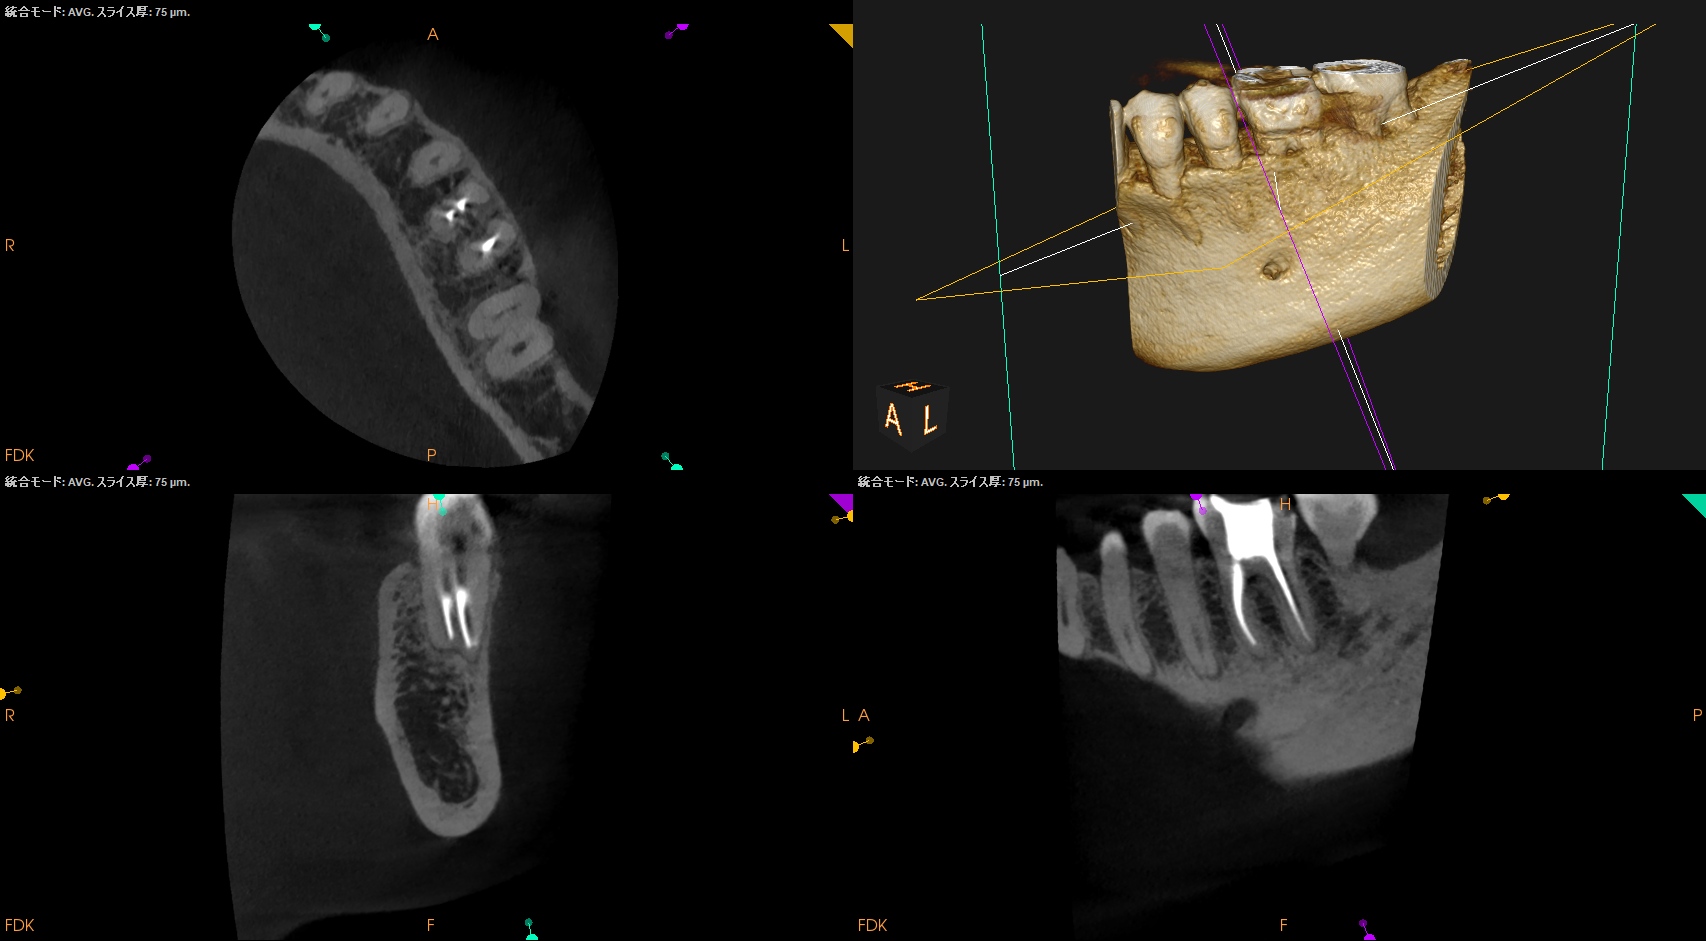

参考ケースは以下だ。

Dにはほぼ歯髄に修復物が覆いかかっている。

これは、

Asymptomatic irreversible pulpitisの可能性が高いだろう。